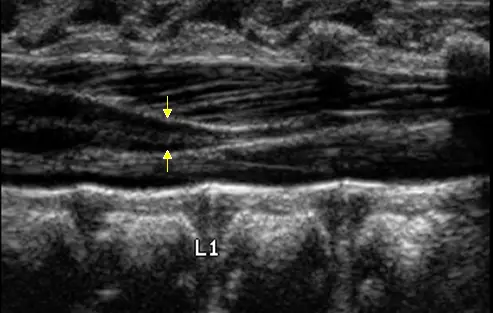

新生兒脊椎超音波檢查如附圖,箭號所指為何?

- 切面與位置:此為新生兒腰椎的矢狀切面(sagittal plane)超音波影像。影像下方可見標示為「L1」的腰椎椎體(lumbar vertebral body)。

- 腦脊髓液包覆著一條低回音(hypoechoic)的管狀構造,且中央有一條明顯的高回音細線(代表脊髓中央管 central canal),此管狀構造即為脊髓。

- 箭號所指處:可以看到脊髓在 L1 的高度逐漸變細,形成一個錐狀(tapering)的末端,這個特徵性的解剖構造即為脊髓圓錐(conus medullaris)。

- 在脊髓圓錐的下方,可以隱約看到多條細長的高回音線條,這些是向尾側延伸的**馬尾(cauda equina)**神經根。